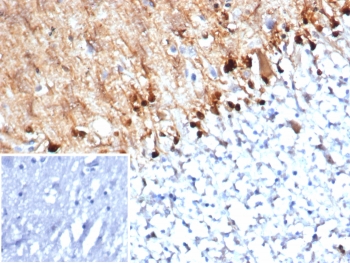

IHC staining of FFPE human brain tissue with S100B antibody (clone S100B/4152) at 2ug/ml. Inset: PBS used in place of primary Ab (secondary Ab negative control). HIER: boil tissue sections in pH 9 10mM Tris with 1mM EDTA for 20 min and allow to cool before testing.